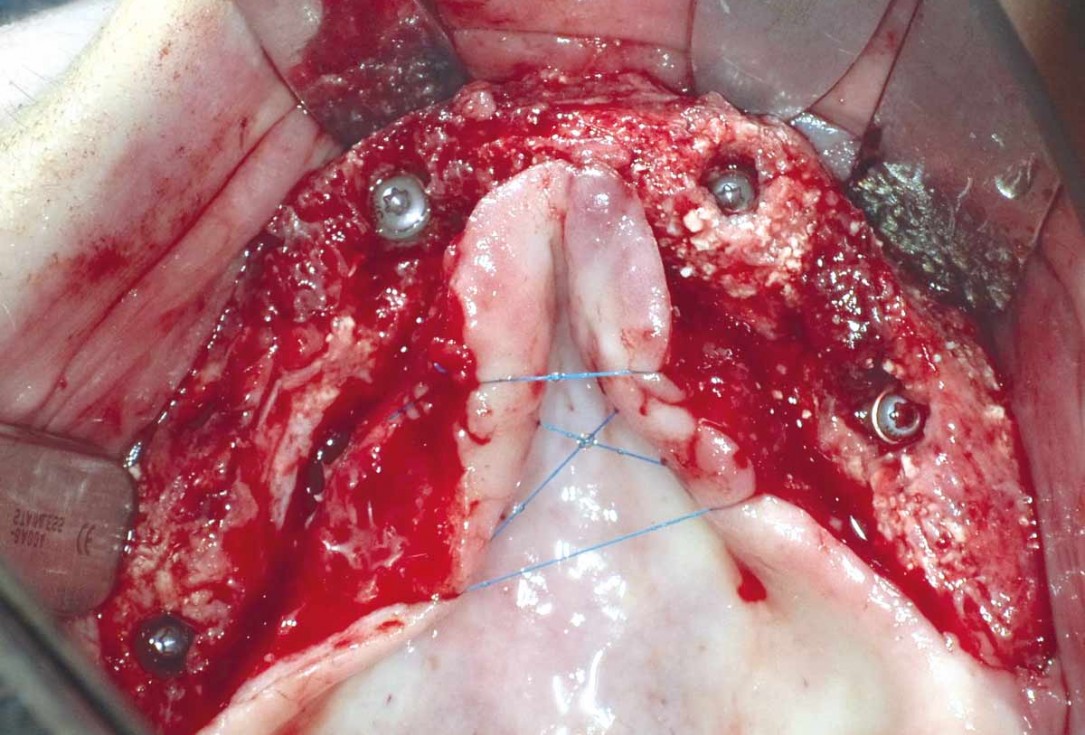

8/23 - Fixation of the first maxgraft® bonebuilder with osteosynthesis screws

Full arch reconstruction of the maxilla with maxgraft® bonebuilder - Dr. M. Erbshäuser